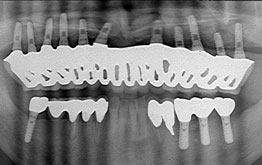

Dさんは、前の歯医者でブリッジの治療を受けていました。

ブリッジは歯がない所に歯をいれる方法ですが、それを支える歯にはかなりの負担がかかる方法です。

多くのパターンとして、負担のかかった歯が負担に耐えられずダメになり、さらに隣の歯に新しいブリッジをかける。というパターンがあります。

それを続けていくと、どんどん隣の歯がダメになり、入れ歯に近づいていくのです。

Dさんはまさにそのパターンでした。

Dさんの下の歯はついに入れ歯になり、上の歯は残りあと5本となり、全部がつながったブリッジは食事中に頻繁にはずれてくるようになりました。

私のところには他のクリニックではインプラント治療ができないと言われた方々がインプラント治療を受けに来院します。

私のところには他のクリニックではインプラント治療ができないと言われた方々がインプラント治療を受けに来院します。

私は何度もHPで書いていますが、「私は全身疾患でもない限りどんなところにでもインプラント治療をすることができます。」私は本当のことを書いているのですが、一般的にはHPは大げさに書かれていることが多いため、私のクリニックに来院した患者さんは「私はインプラントできますか?」と聞いてきます。

もちろん答えは「YES」です。

私は私が開発して発表した新しいテクニックを自由に使うことができます。それは決して大げさな手術ではなく、今まで大げさな手術でなければできなかったことが簡単にできるのです。

私は毎月の私のセミナーに来る歯科医師たちに、『インプラントの手術をしても患者さんが「なーんだ、普通の歯の治療と変わらないな」と思えるような手術をするべき』と説いています。

私のテクニックを使うとどんなところにもインプラントを埋入できるのです。

私のところでは、大学病院で断られた方々も来院します。そのような方も完成して治療の最後に「私でもインプラントができたのですね!」と笑ってくれます。私は困難な症例ほどやりがいを感じます。あきらめないことが肝心なのです。

Aさんの場合

Aさんは30代女性で、人より痛みに対して敏感です。普通の人がさほど苦痛でないような治療でもAさんにとっては何倍もつらいのです。

そのため歯科治療を受けることがおっくうになり、上の奥歯がどんどん悪くなってしまったのです。

でもAさんは手術の恐怖や高額な費用にもかかわらず、将来のことを考えインプラント治療に踏み切ることにしました。

Aさんは、まず大学病院でのインプラント治療を考え、千代田区のある大学病院のインプラント科に行きました。ところがAさんの顎の骨はかなり少なくなっており、「インプラントの手術はできません」と言われてしまったのです。

「せっかく勇気をふりしぼって決心したのに、インプラント手術ができないなんて。。。。」

Aさんはインプラント専門医をいろいろ探し、私のところにたどり着きました。

検査後、私から「問題なくできますよ」と言われ、インプラント治療に入りました。

治療は私の開発したオステオプッシャーを使用した為、最小の侵襲でかつ確実な結果を生みました。 数ヶ月後、白くてきれいな左右の歯を手に入れたAさんは、とても明るく「あきらめないで本当に良かった」と言ってくれました。

これが、新しい方法なのです。テクニックは進歩しているのです。